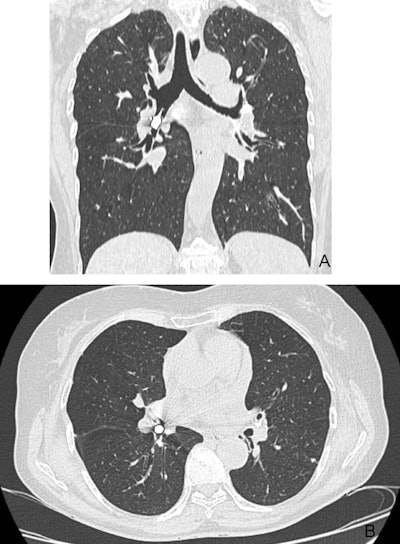

First, a chest x-ray was completed, which showed a 2-cm metallic foreign body within the patient's right airway. The object was consistent with a dental drill head that had been aspirated, the authors wrote.

Figure 1: Posteroanterior chest x-ray. A metallic foreign body (the drill head) is visible near the right hilum, supposedly located in the right airways. Images and captions courtesy of De Chiara et al. Licensed under CC BY-NC-ND 4.0.